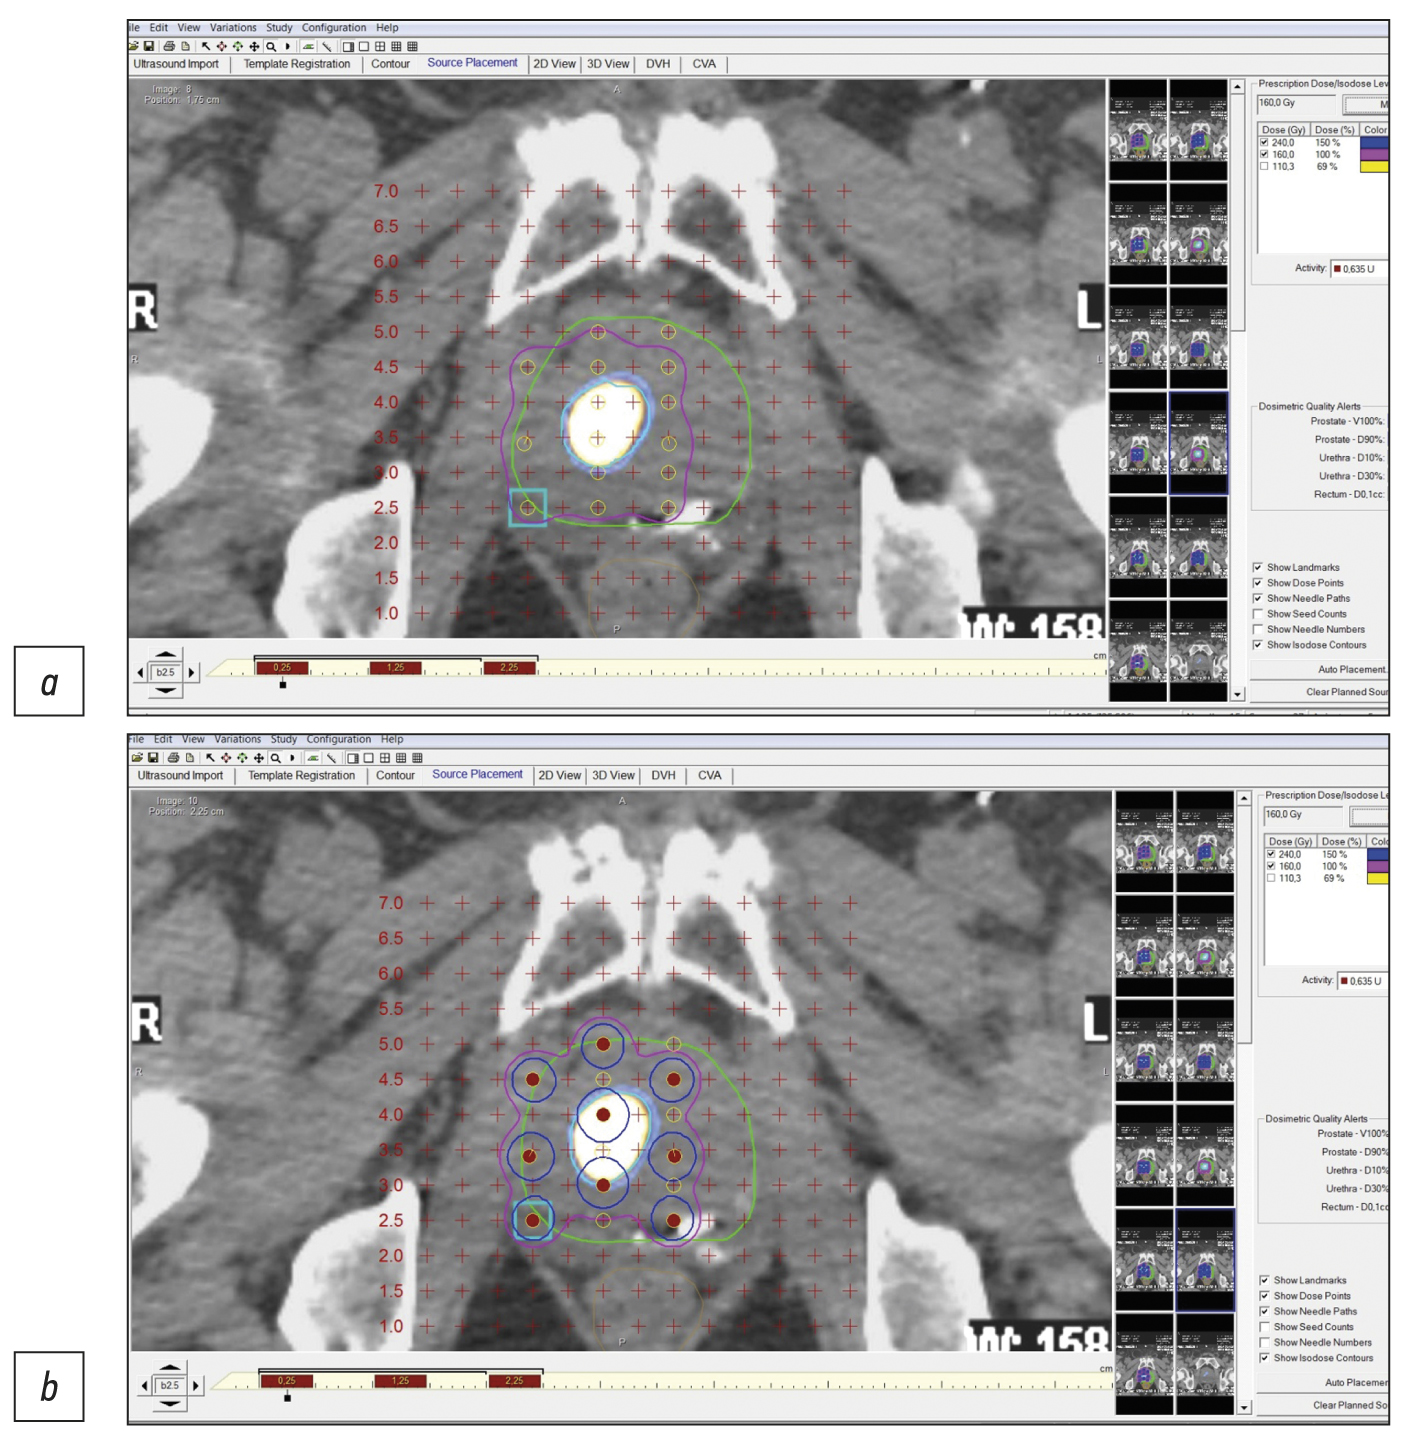

Одним из методов лечения локализованного рака предстательной железы без признаков прорастания капсулы железы и в отсутствии признаков метастазов (стадия cT1-T2N0M0) является брахитерапия с имплантацией микроисточников на основе изотопа 125I. Методы структурной визуализации (ультразвуковое исследование; компьютерная томография, КТ; магнитно-резонансная томография, МРТ) не обладают высокой специфичностью в дифференциальной диагностике рака предстательной железы. Гибридные технологии лучевой визуализации (однофотонная эмиссионная компьютерная томография + компьютерная томография, ОФЭКТ/КТ; позитронно-эмиссионная томография + компьютерная томография, ПЭТ-КТ; позитронно-эмиссионная томография + магнитно-резонансная томография, ПЭТ/МРТ) сочетают в себе достоинства высокой чувствительности кросс-секционных методов структурной визуализации (КТ и МРТ) и высокой специфичности методов молекулярной визуализации (ОФЭКТ, ПЭТ) с туморотропными радиофармацевтическими лекарственными препаратами.

В данной работе на 7 клинических наблюдениях локализованного рака предстательной железы (шкала Глисона 6–7) показано, что прецизионность низкодозной брахитерапии микроисточниками 125I локализованных карцином предстательной железы, равно как и прицельной биопсии, может быть повышена при использовании гибридных методов ПСМА-рецепторной (простатспецифический мембранный антиген) молекулярной визуализации (ОФЭКТ/КТ, ПЭТ/КТ). Метод ОФЭКТ/КТ более доступен, чем ПЭТ/КТ, и при наличии холодных наборов (HYNIC-PSMA) позволяет выполнять исследование в любой лаборатории радиоизотопной диагностики, располагающей соответствующими сканерами.

Инновационная технология ПСМА-навигационной биопсии и брахитерапии под контролем гибридной молекулярной визуализации может применяться при первичных и рецидивных случаях локализованного рака предстательной железы, увеличивает точность и снижает травматичность процедур, повышает медико-экономическую эффективность низкодозной брахитерапии микроисточниками 125I.